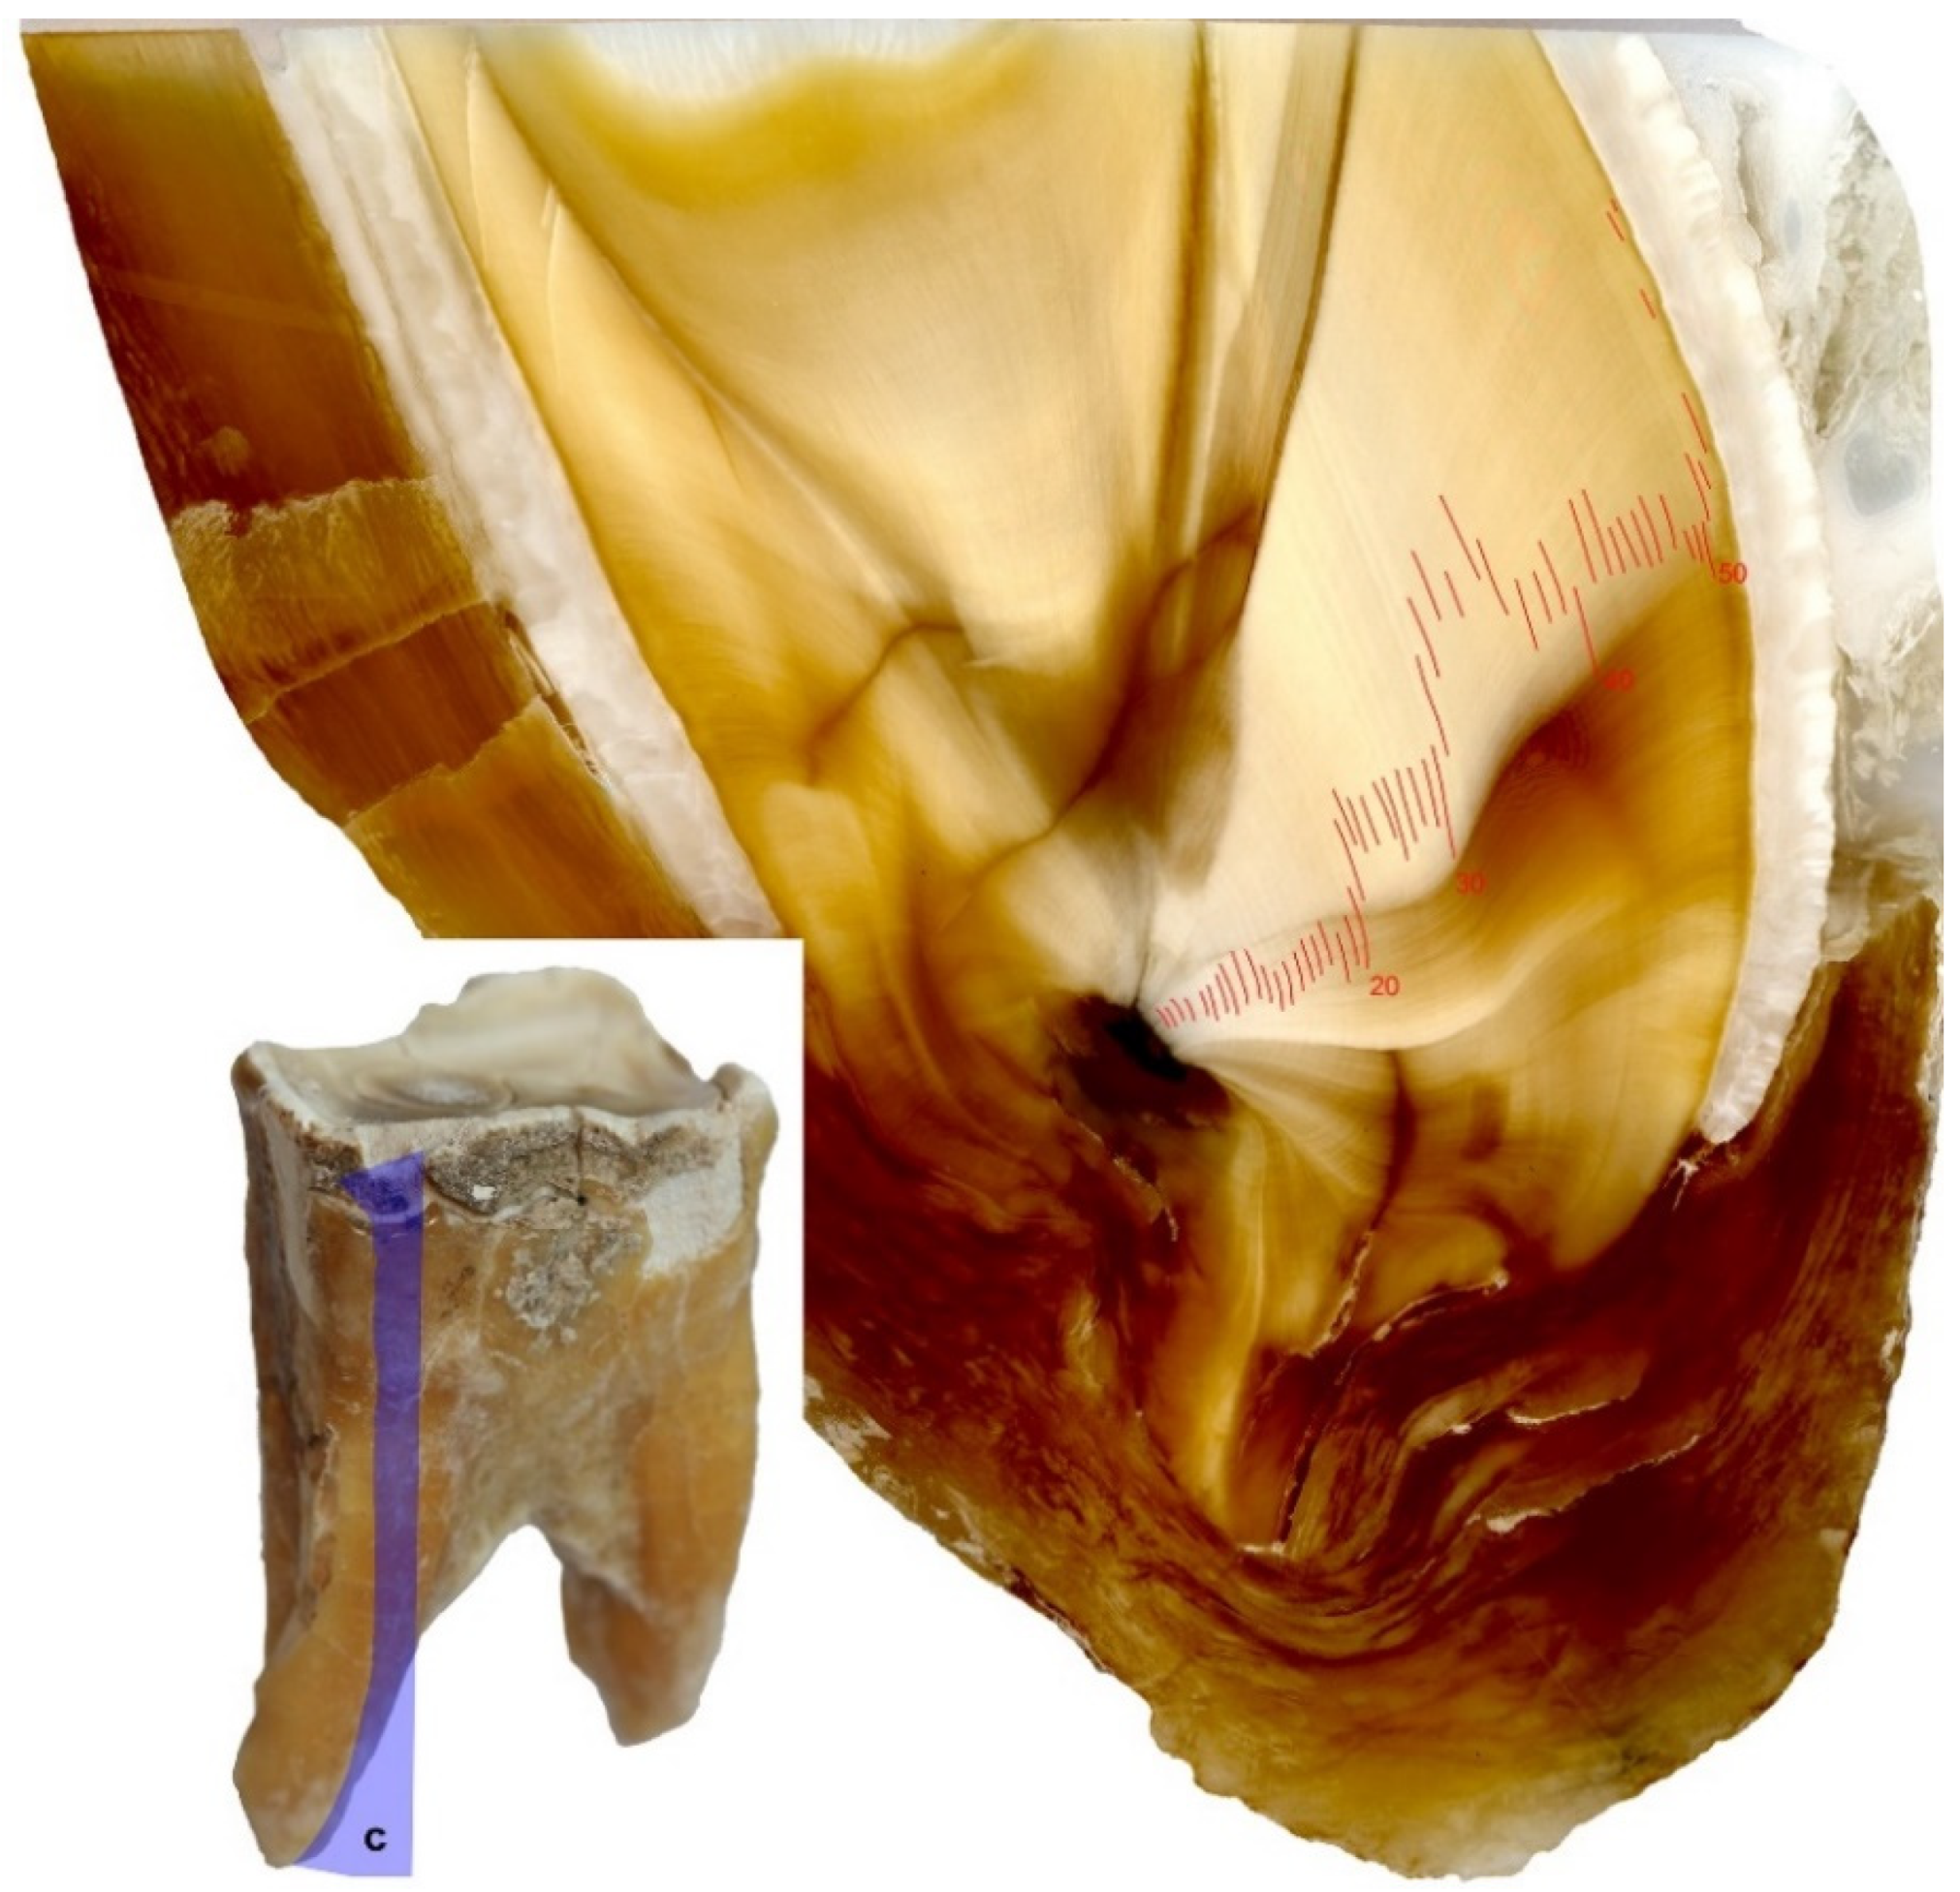

- longitudinal sections in a lingual-buccal plane through the crown and the root—cutting planes routed through the middle of the rostral and caudal roots.

2.4. Annual Season Analysis Based on Cement Lines

3.1. Analysis of Tooth Sections

3.2. Analysis of Seasonality Based on Cement Lines